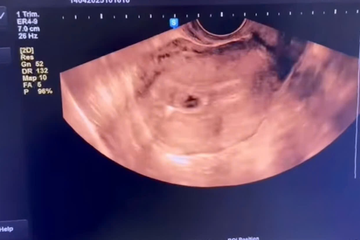

Người phụ nữ mang thai dù đặt vòng từ 4 năm trước

Người phụ nữ đi khám sức khỏe vì có triệu chứng ốm nghén và phát hiện có bầu dù trước đó đã đặt vòng tránh thai.